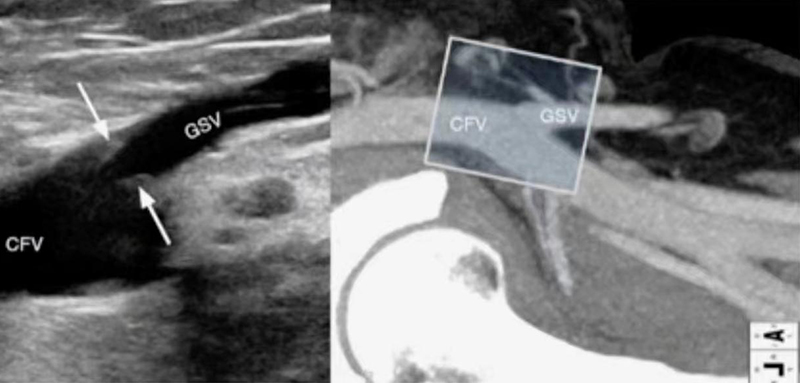

多普勒血管超声定位